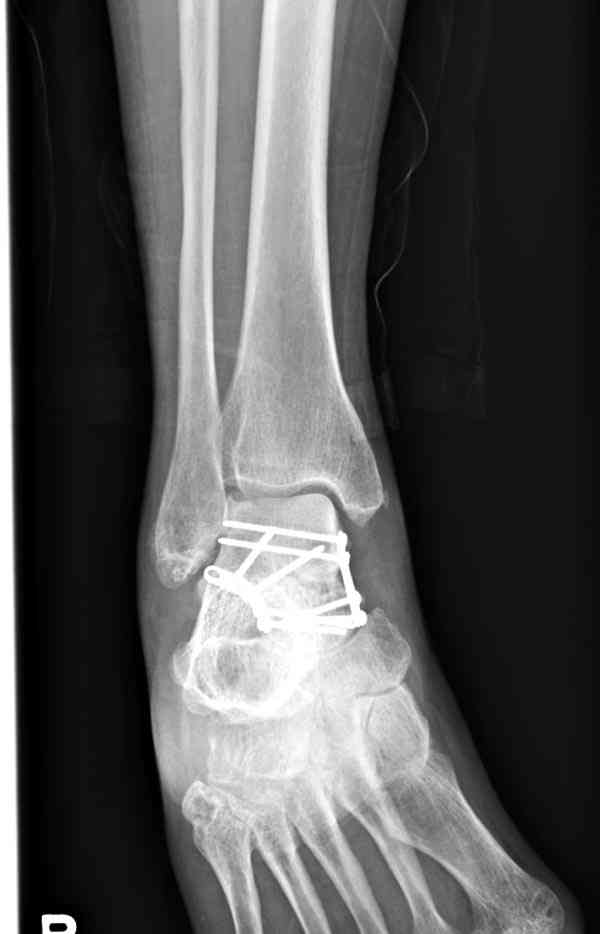

Случай с множественным оскольчатым переломом тарана оперированный из двойного доступа.

Через 8 мес.: